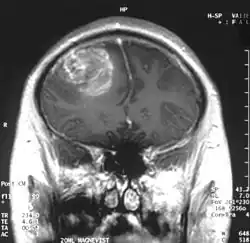

W obrazowaniu metodą rezonansu magnetycznego stwierdza się guz o niejednorodnym sygnale, ze współistniejącymi zmianami wstecznymi. Glejak wielopostaciowy ulega silnemu, nieregularnemu, brzeżnemu wzmocnieniu kontrastowemu.

W tomografii komputerowej guz objawia się w początkowym okresie jako ognisko hipodensyjne, nie ulega wzmocnieniu po podaniu kontrastu. Później współczynnik osłabienia jest zróżnicowany, ognisko ma nieregularne granice i otoczone jest szerokim pasmem obrzęku.